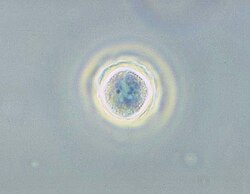

Phase contrast micrograph of an Acanthamoeba polyphaga cyst. | |